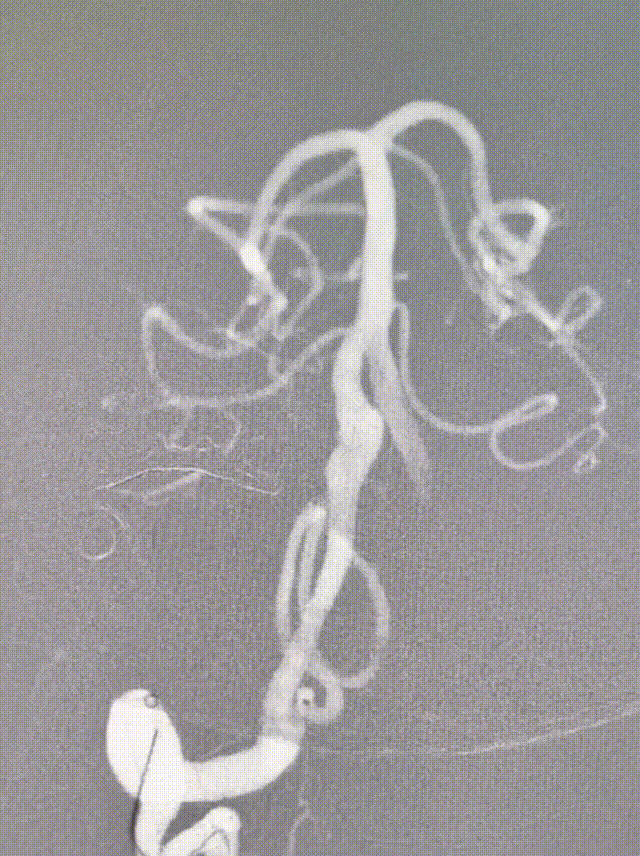

经桡动脉穿刺,132cm Simmons导管带7F 105 EasyRadial™输送导管过弓成攀超选右侧椎动脉。

132cm Simmons导管送至V2段末端输送导管。

微导丝带XT-27微导管至基底动脉尖。

将EasyRadial™输送导管送至V3段保持支撑。

造影测量血管直径3.5,选择4.0*30mm 密网支架释放。

密网支架释放完毕造影,显示支架打开良好。

将EasyRadial™输送导管撤至近端V2段动脉瘤处,释放7.0*40mm 血管支架。

血管支架释放完毕造影,手术结束。